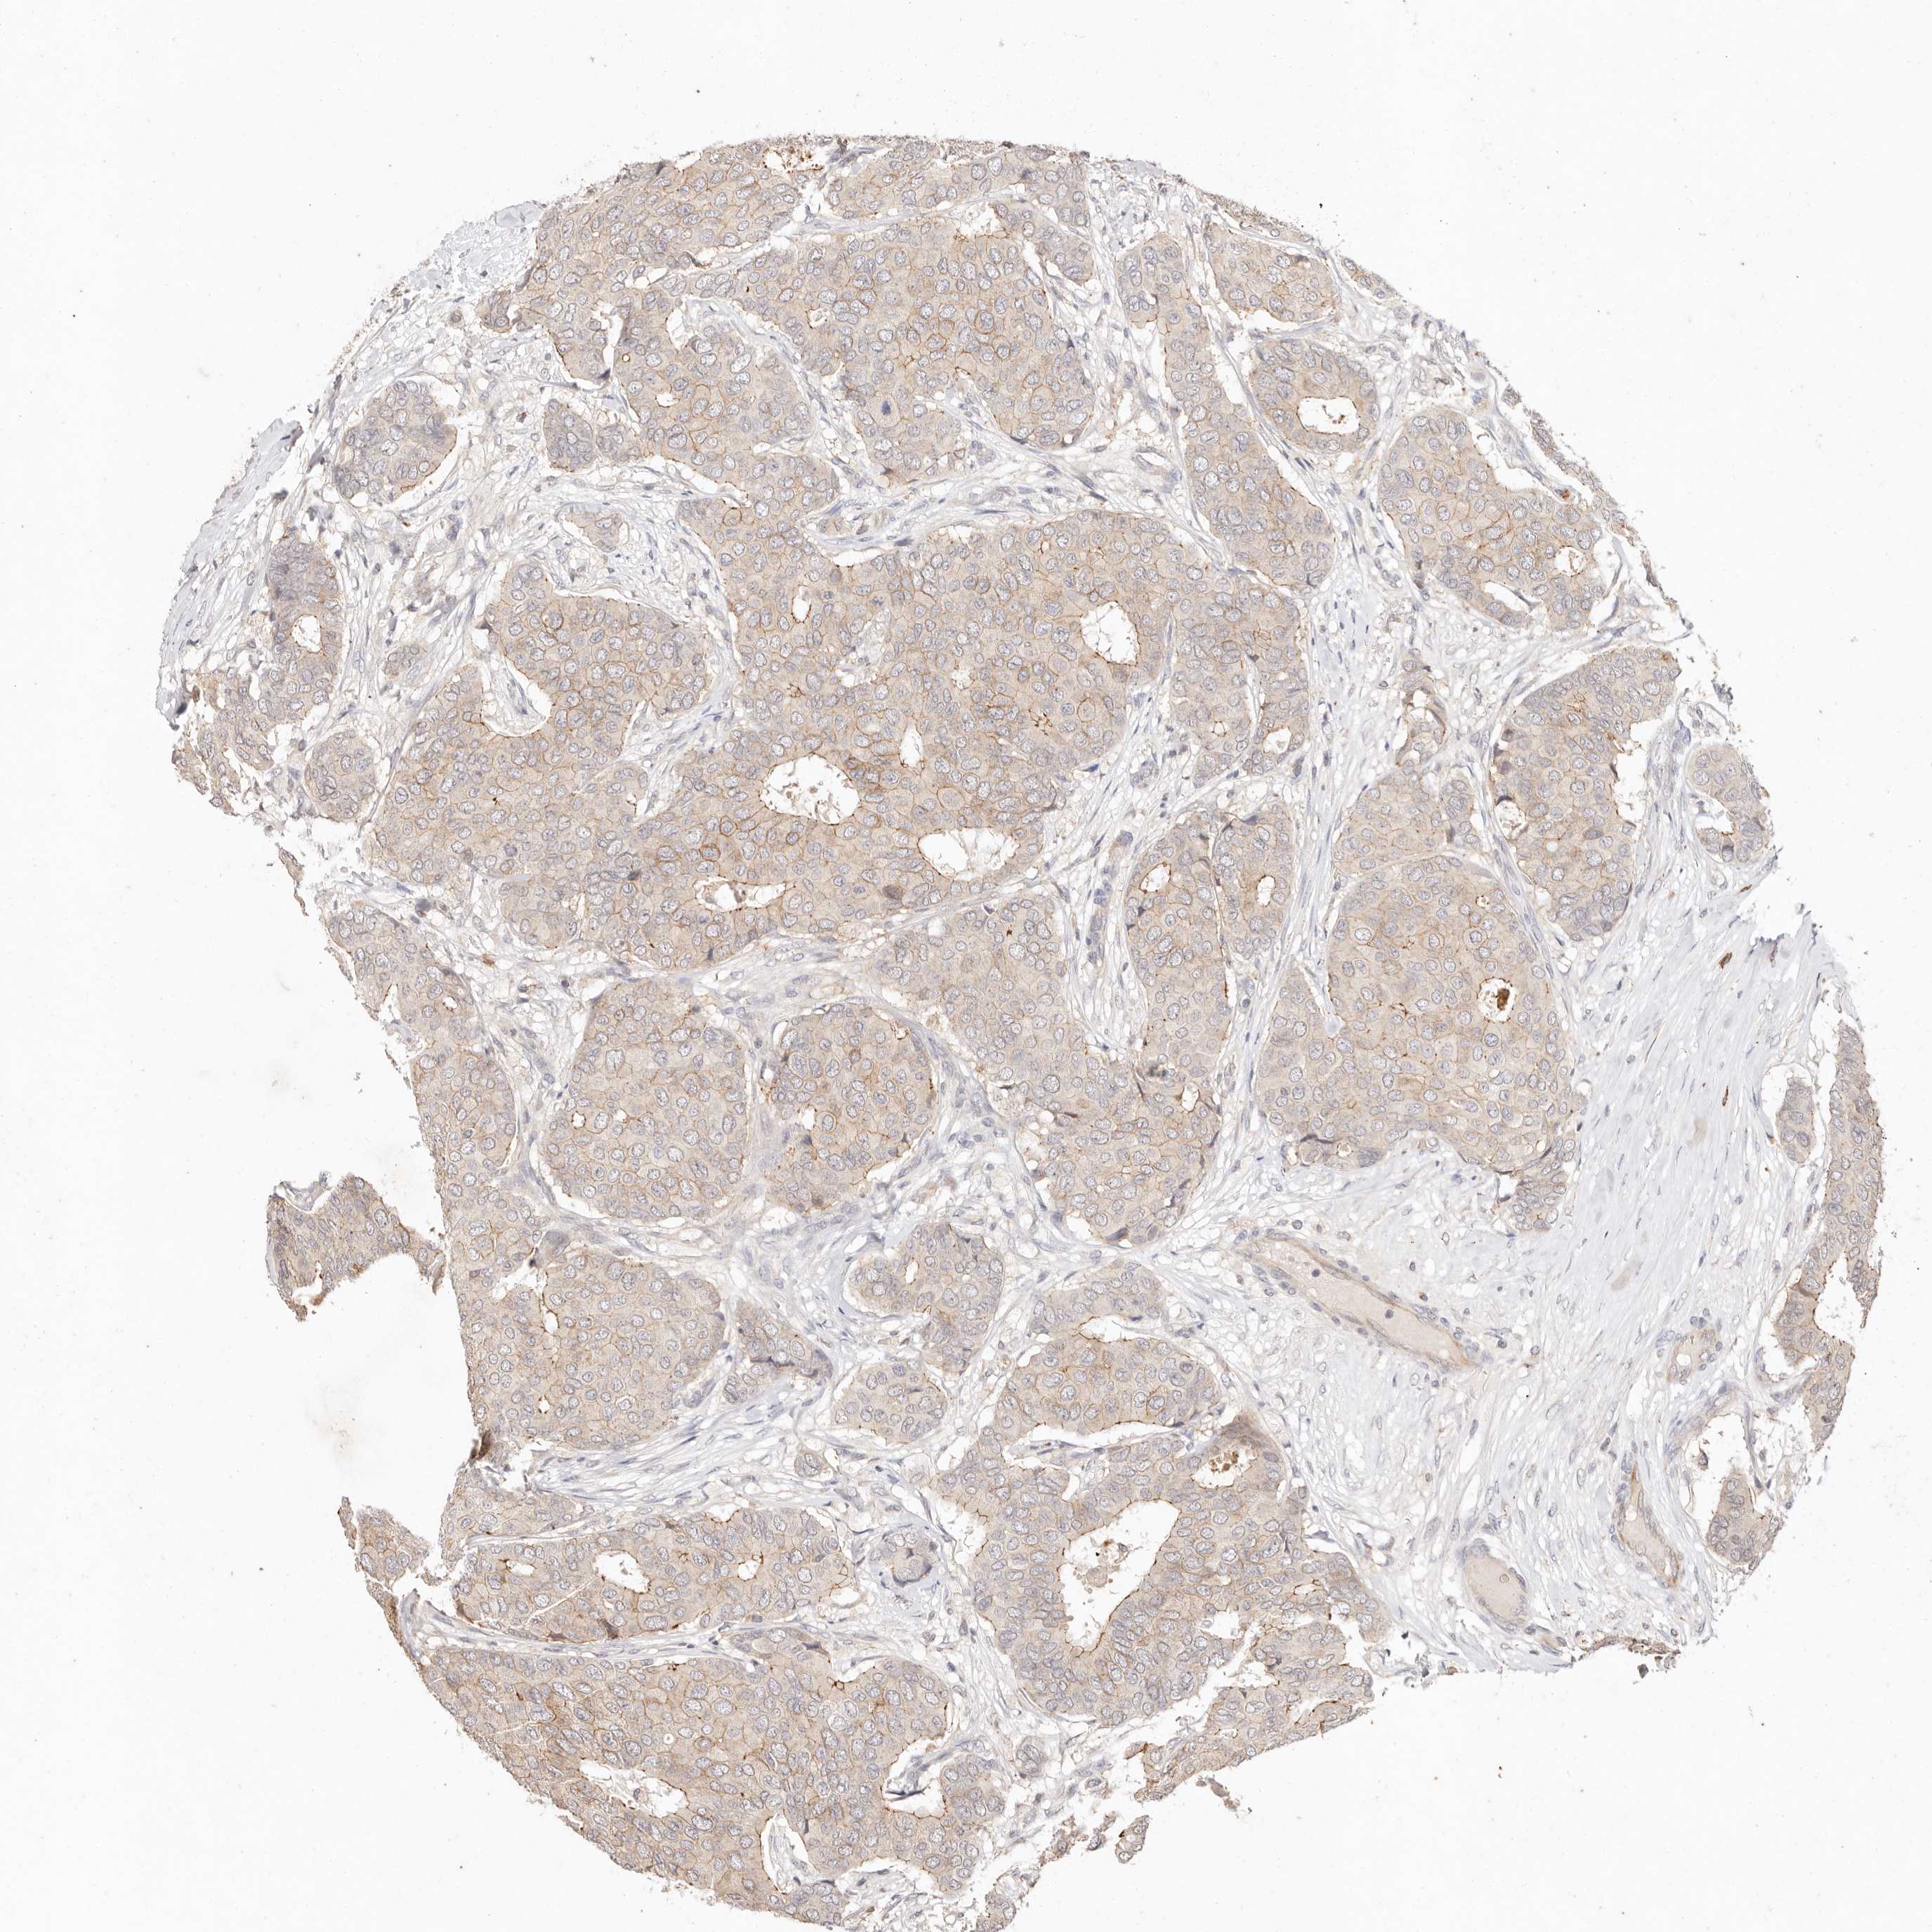

CANCER BREAST CANCER Show tissue menu

BRCA TCGA BRCA VALIDATION PROTEIN EXPRESSION

Breast cancer

Human cancer

Breast invasive carcinoma